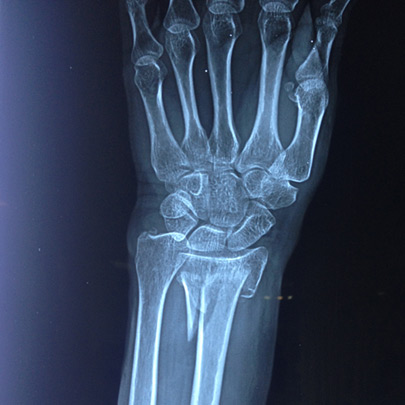

Fracturas y luxaciones